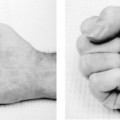

Swelling and ecchymosis were noted, centered over the dorsal ulnar half of the hand. When viewed dorsally, the fifth metacarpal head lacked the prominence of the other digits. Tenderness was maximal at the fifth metacarpal neck, and palmar palpation revealed fullness at the level of the metacarpophalangeal (MP) joint. When the patient was asked to actively extend his small finger, the MP joint hyperextended 5 degrees, but he was unable to fully extend his proximal interphalangeal (PIP) joint (minus 20 degrees of full extension). When the patient made a fist, the small finger rotated toward the thenar eminence and was overlapped by the ring finger. There were no open wounds, and no other areas of tenderness localized. Two-point discrimination and vascular status were intact.

- Examine for malrotation or pseudoclawing on extension.